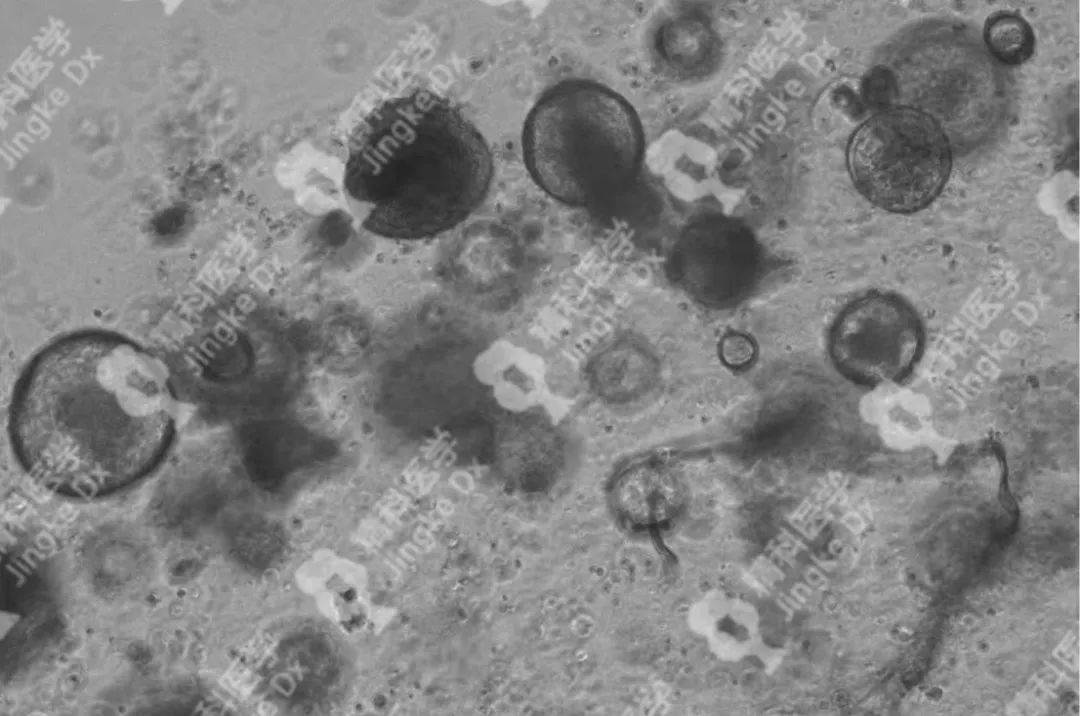

精科類器官培養(yǎng)相關(guān)服務(wù) 精科醫(yī)學(xué)作為類器官技術(shù)轉(zhuǎn)化先行者致力于推動(dòng)類器官技術(shù)的轉(zhuǎn)化與應(yīng)用,對(duì)基于類器官培養(yǎng)擁有成熟的技術(shù)與經(jīng)驗(yàn)。精科類器官團(tuán)隊(duì)技術(shù)深耕十余年,擁有國內(nèi)頂級(jí)的類器官團(tuán)隊(duì),超微量建模技術(shù)成功率高達(dá)95%以上,有成功建模30+種腫瘤的經(jīng)驗(yàn)(包括上述子宮內(nèi)膜癌、宮頸癌和卵巢癌)。可以提供包含類器官建模與保存(建模、凍存、傳代)、類器官檢測(cè)(類器官H&E染色、免疫組化、藥物敏感度篩選)等多種類器官相關(guān)服務(wù)。檢測(cè)服務(wù)最快可在十個(gè)工作日內(nèi)完成,更好為患者爭(zhēng)取治療時(shí)間。 ★ PIC.01 精科卵巢癌類器官圖像 ★ PIC.02 精科宮頸癌類器官圖像 ★ PIC.03 精科子宮內(nèi)膜癌類器官圖像

★ PIC.04 精科類器官培養(yǎng)其他腫瘤圖像示例